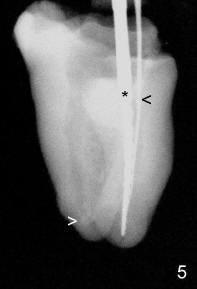

The most apical portion of the distal canal is found to be blocked (Fig.5 white >) when filling material is removed. The blockage is pre-existing, since it is present in Fig.2 and 4. The mesiobuccal canal (Fig.5 black <, #10 hand file) fuses with the mesiolingual canal (*, 30/.06 rotary file) before exit at apical foramen.

In brief, RCT failure in this case is both endodontic (short fill, and missing MB canal) and restorative (coronal leakage: crown open margin, no filling material/cement in pulpal chamber and around the post).